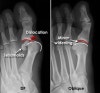

X-ray : 발가락 관절의 탈구(MTPJ Dislocation)

X-ray 촬영을 실시합니다.